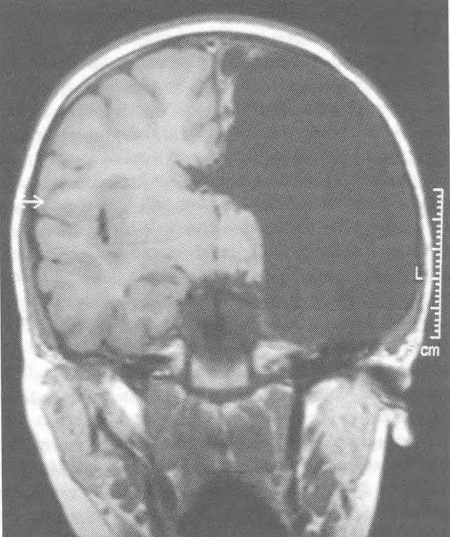

В детстве, примерно до четырехлетнего возраста, мозг поразительно пластичен. Есть свидетельства, что в этот период около сотни тысяч синапсов погибают и заменяются новыми каждую секунду [32]. Проявление крайности в сфере нейропластичности – случай трехлетней девочки, левое полушарие головного мозга которой пришлось удалить хирургическим путем из-за тяжелого хронического энцефалита с симптомами эпилепсии (см. рис. на с. 245). Врачи больницы Джона Хопкинса в Балтиморе провели эту серьезную операцию на мозге как минимум для сотни малолетних детей, многие из которых страдали стойкой эпилепсией, вызванной тяжелыми нарушениями нервно-психического развития. Если такое же хирургическое вмешательство переносили взрослые, последствия оказывались катастрофическими: пациенты теряли способность говорить или понимать язык, у них парализовало правую сторону, они слепли на один глаз. Но у этой девочки уже на следующий год после операции почти не проявлялись симптомы. Односторонний паралич практически исчез, она могла мыслить ясно. Сейчас она развивается нормально, бегло говорит на двух языках, бегает и прыгает, хорошо успевает в школе [33].

Иллюстрация к книге — Сознание за пределами жизни. Наука о жизни после смерти [i_022.jpg]

Снимок фМРТ трехлетней девочки после удаления левой половины мозга (на снимке справа)